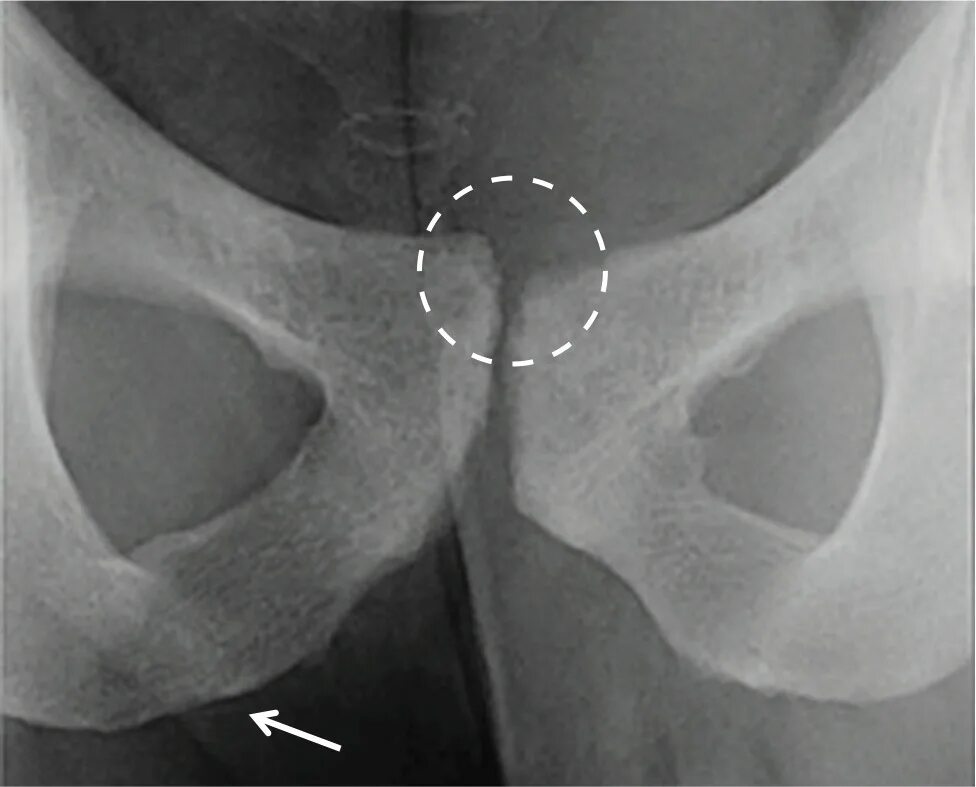

Боль в лонном сочленении